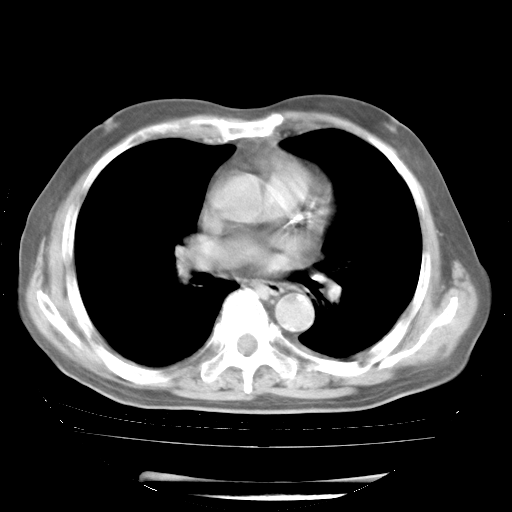

4月28日肺部CT——再次出现类似去年5月9日——透光度降低,“间质性”改变。